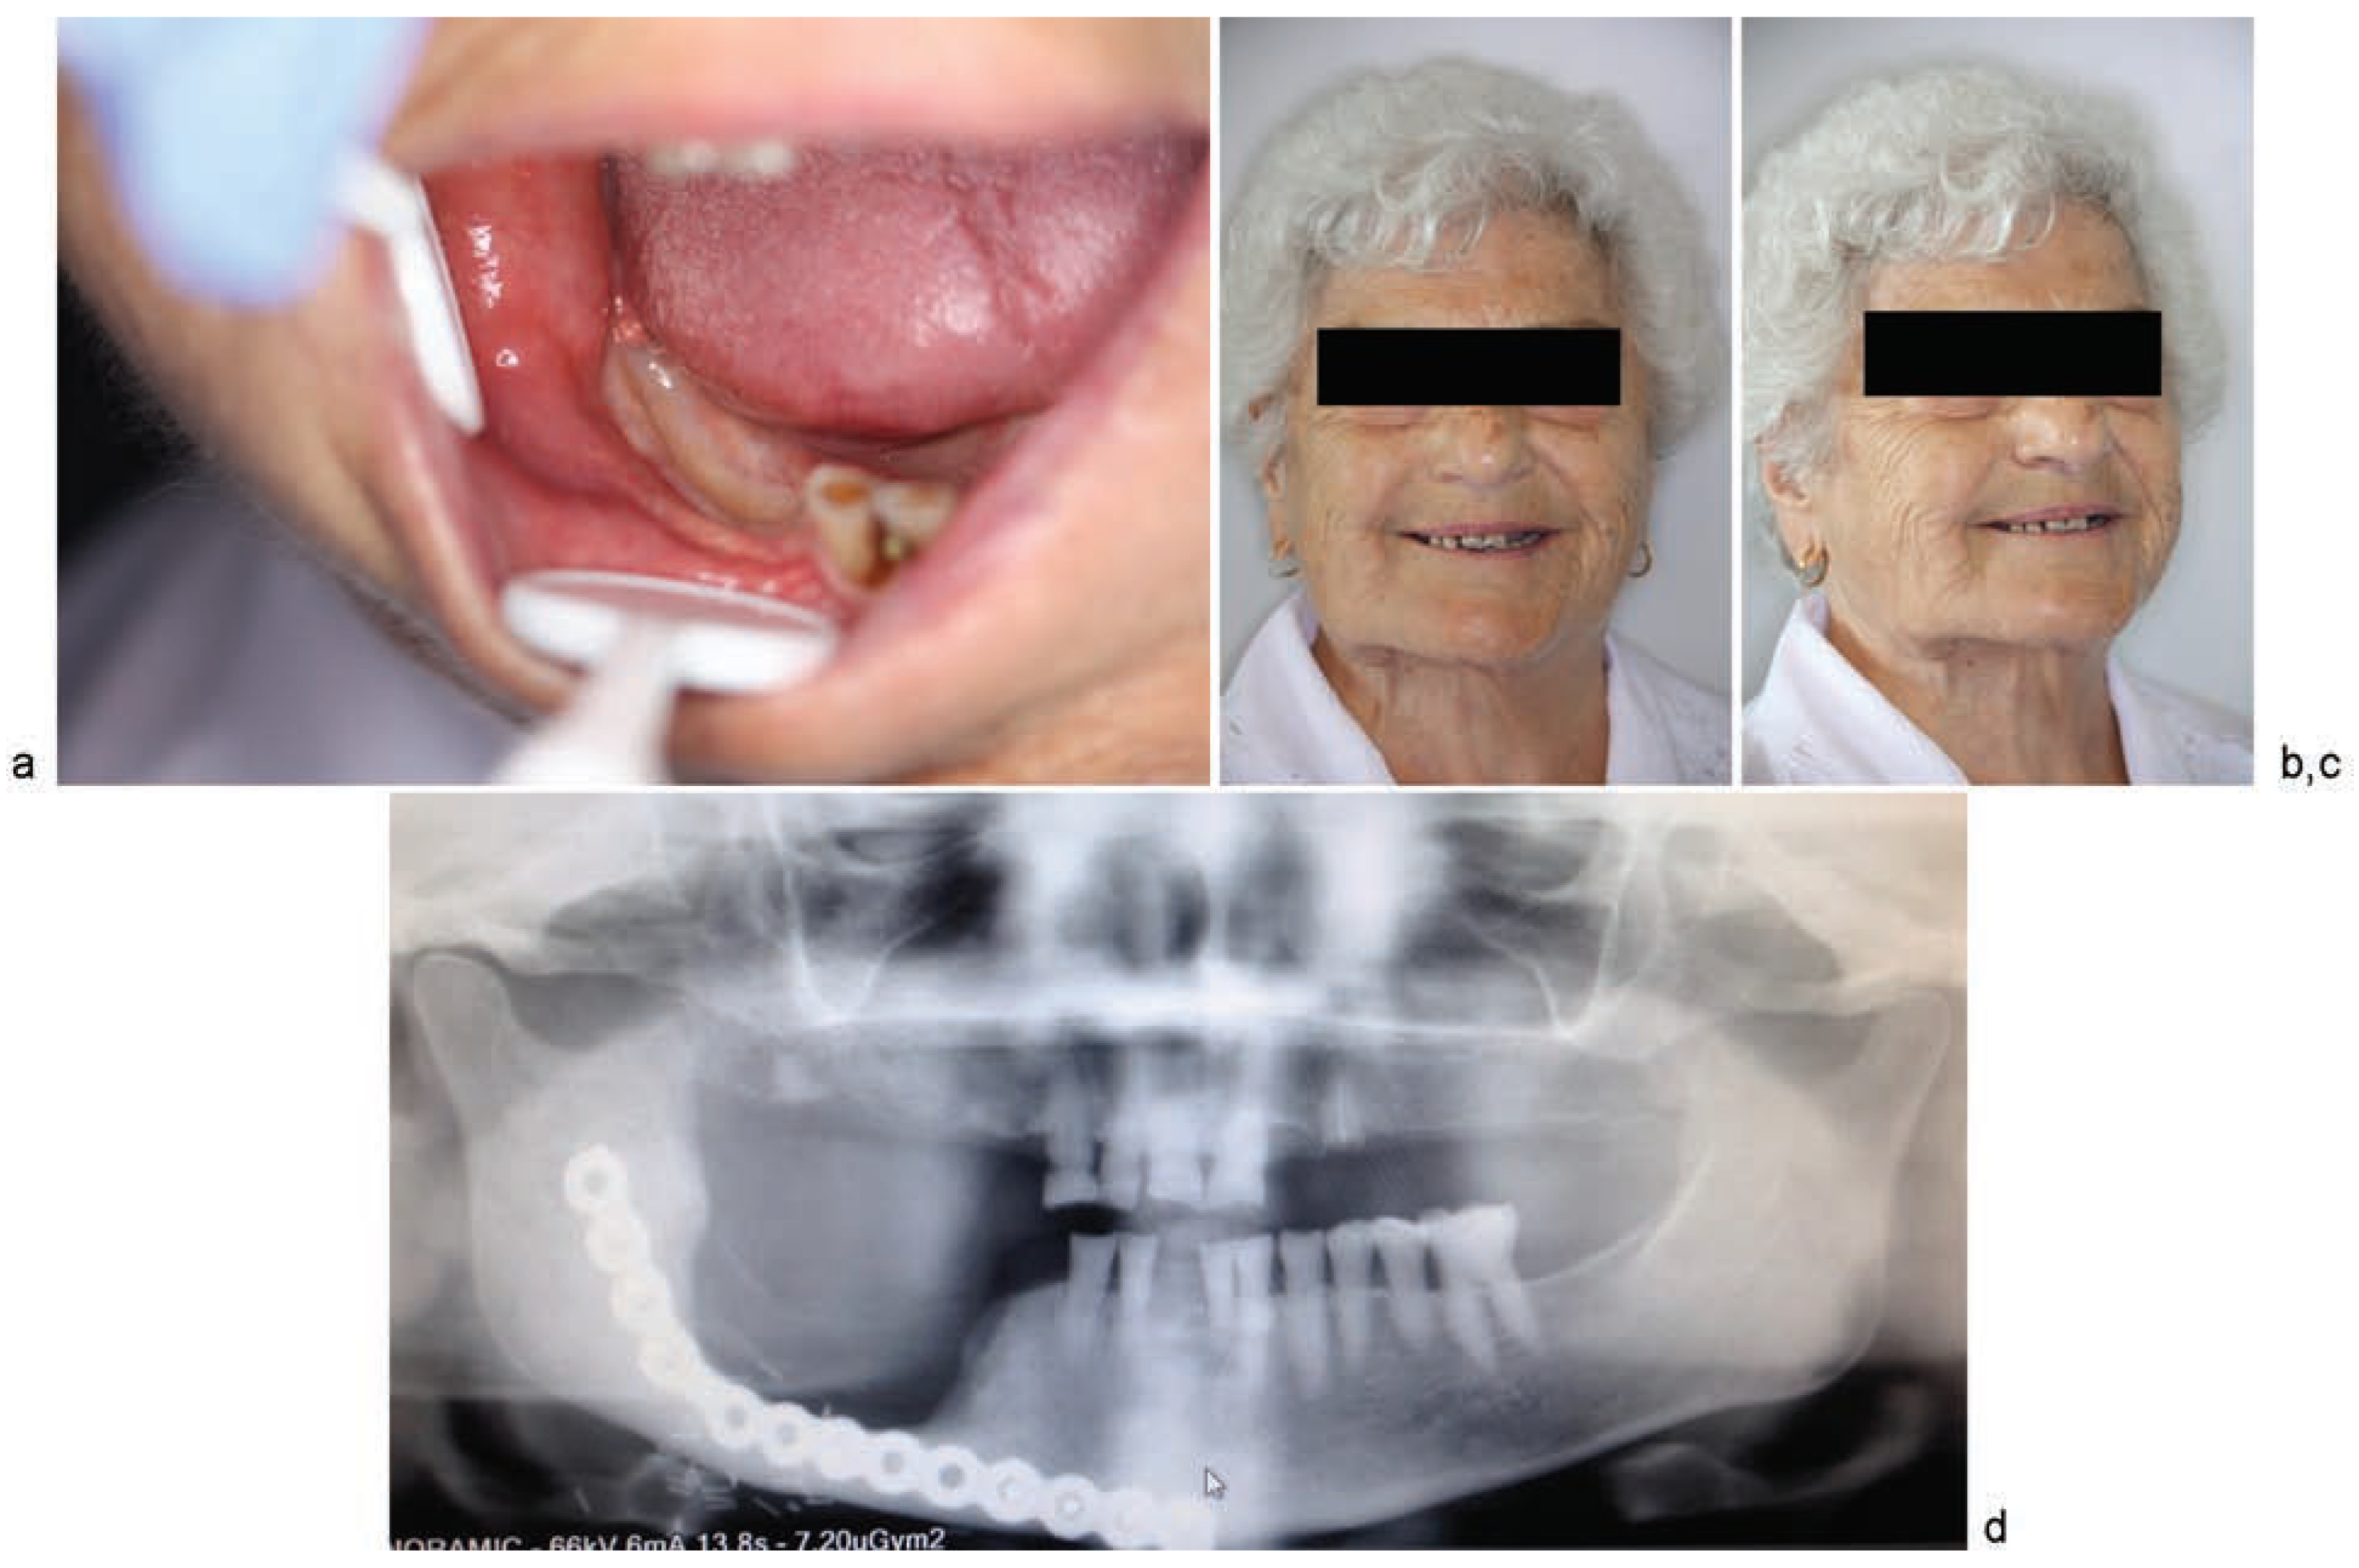

Clinical Cases